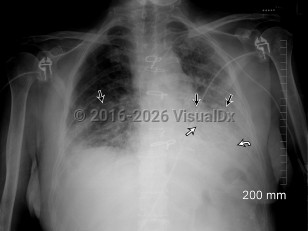

Acute eosinophilic pneumoniaAcute eosinophilic pneumonia

Acute interstitial pneumoniaAcute interstitial pneumonia